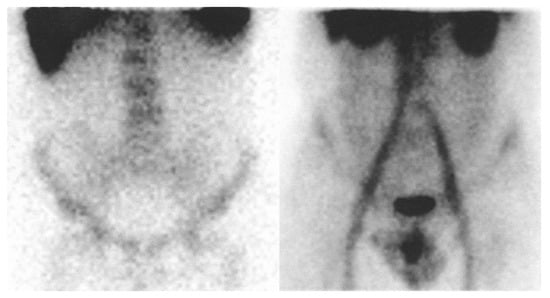

2.2.1. White Blood Cell Scintigraphy

2.2.2. Scintigraphy with Human Polyclonal Immunoglobulin G Labeled with 99mTc

2.2.3. Evaluation of Bowel Abnormalities on Scintigraphy with White Blood Cells and With Human Polyclonal IgG